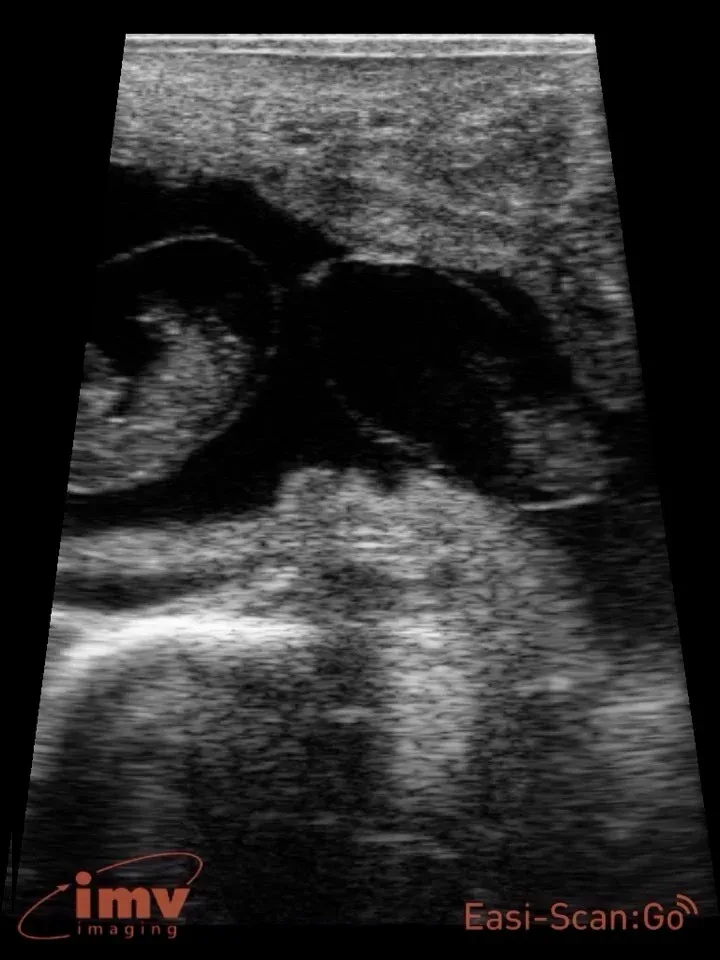

Twins

Image of Twins taken with Easi-Scan:Go

Twin diagnosis: Cows carrying twin pregnancies can be accurately identified using transrectal ultrasonography 40 to 55 days after AI; the entire length of both uterine horns must be carefully scanned to ensure that an embryo is not missed. Because the majority of twins in dairy cattle occurs due to double ovulations, the presence of two or more CL on the ovaries is an excellent indicator of cows with an increased risk of conceiving twins. Several management scenarios could be considered upon identification of a cow carrying twins including culling, abortion and rebreeding, or continued management until parturition.